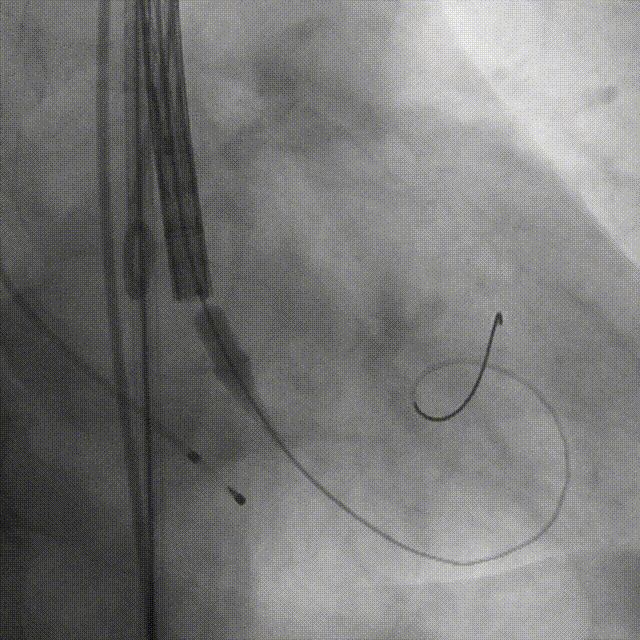

手术过程

导丝跨瓣